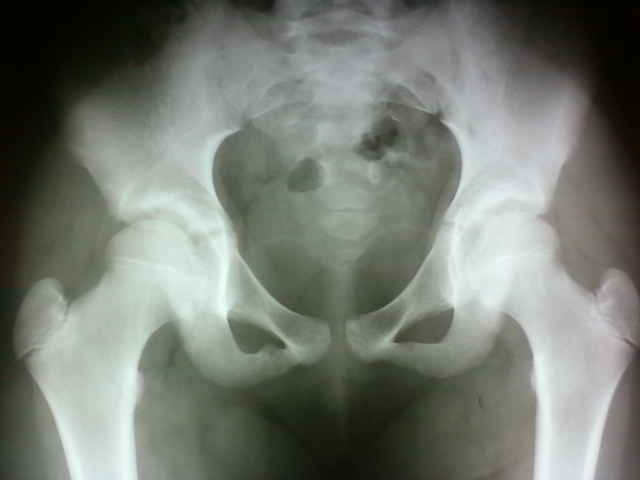

Совсем недавно был подобный случай, описала как асимметричное синостозирование лонной и седалищной костей (происходит до 13 лет), так как клиники нет вообще, случайная находка.

Работаю в детской клиники и недавно сам встретился с подобной картиной. Посмотрел в учебнике Садофьевой - данное состояние описывается как вариант возрастной нормы.

Лоозеровская зона ветви правой седалищной кости. Ведь травмы не было? Я правильно понял?

ТРАВМЫ НЕ БЫЛО

Я полагаю, драгоценнейший Илья Васильевич, что это вариант перестройки костной структуры в результате воздействия длительных интенсивных нагрузок. Распросите родителей, возможно, она начинающая гимнастка или фигуристка? А может она ничем не занимается, кроме шахмат, но в тайне ото всех упорно пытается сесть на шпагат. Я не знаток психологии девочек-подростков, но направление моей мысли, думаю понятно.